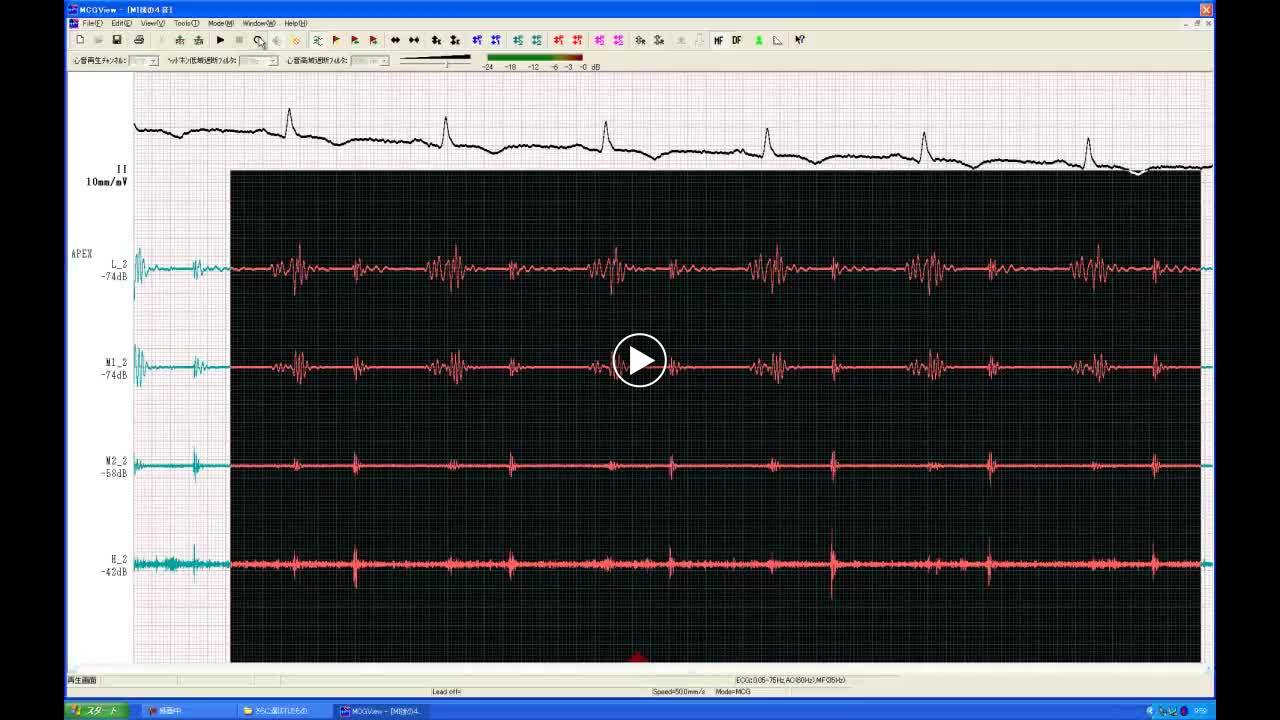

• 図3 心筋梗塞後に聴かれるⅣ音